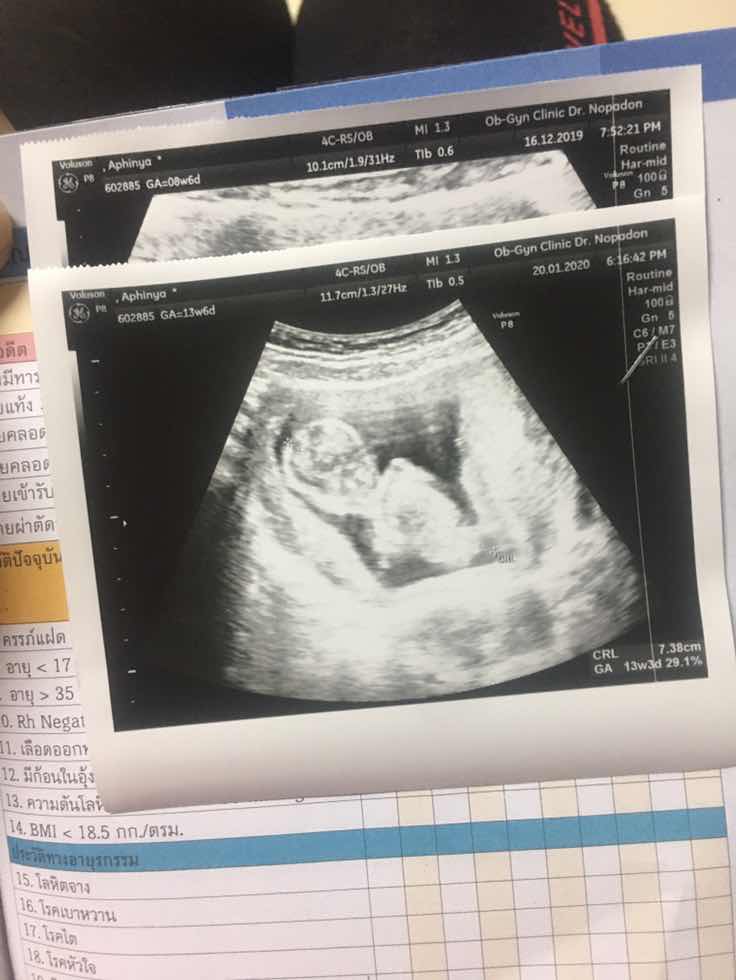

ตอน13w ปัจจุบัน20w ผชจ้า🥰